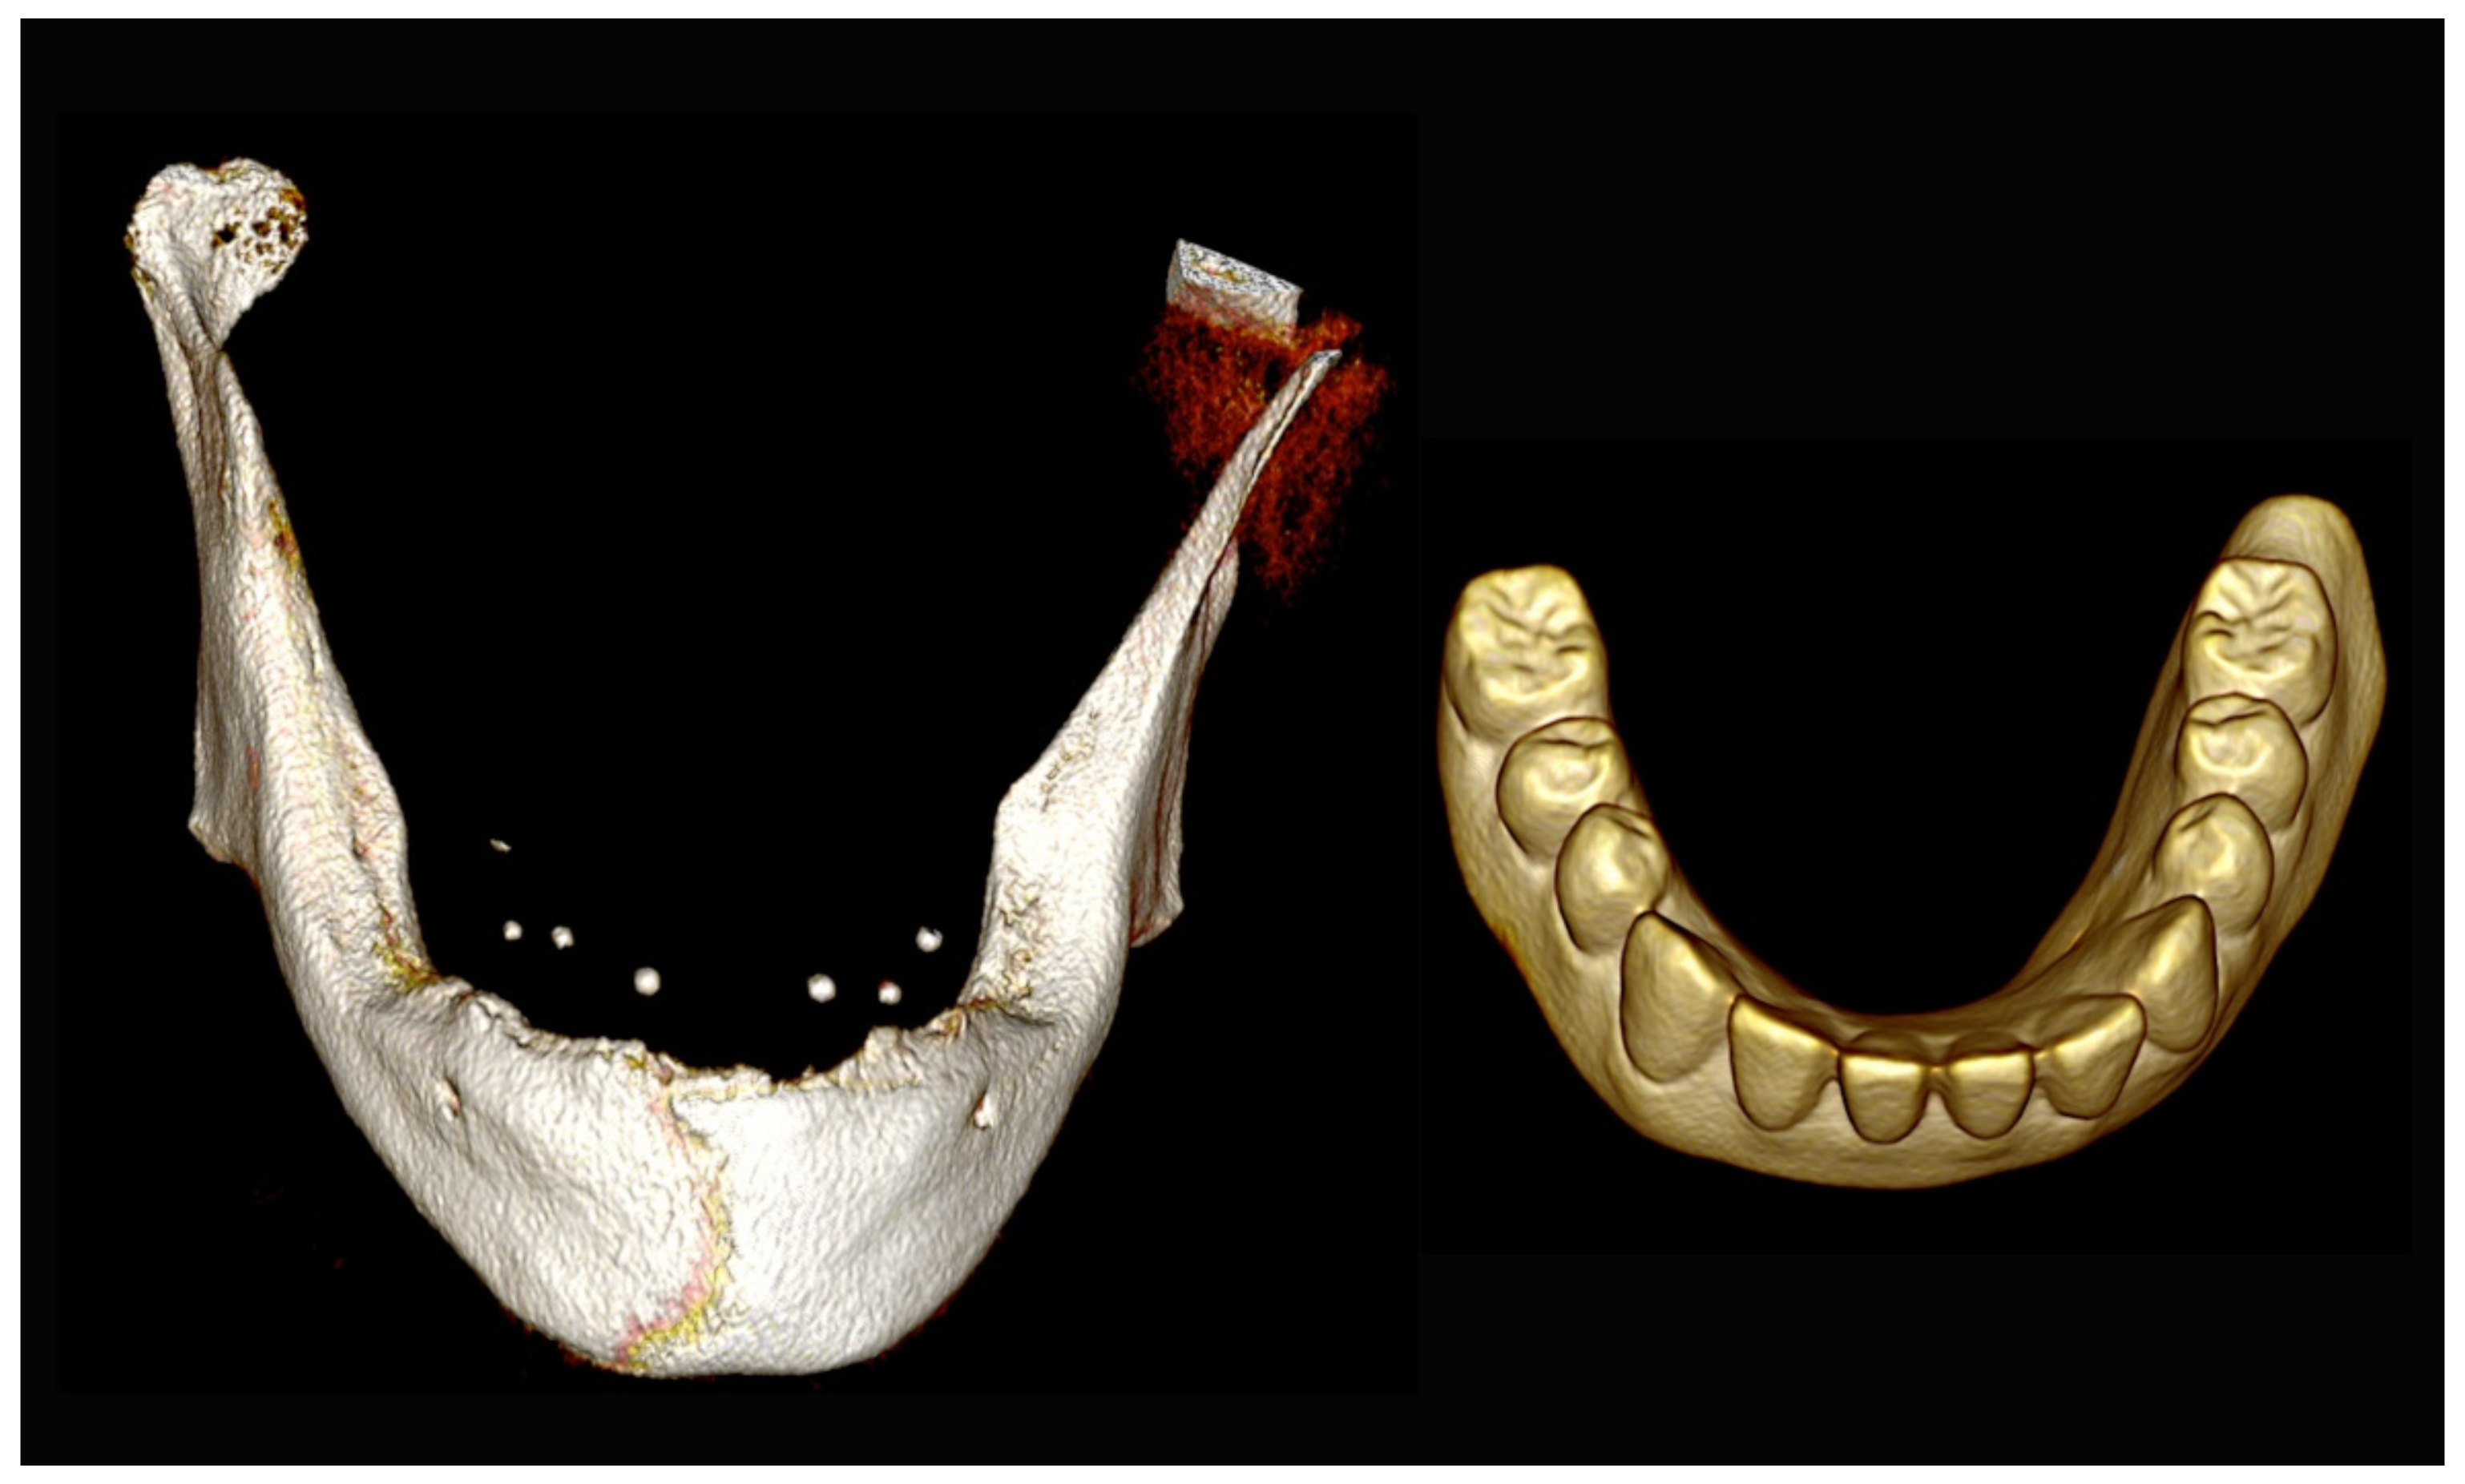

6.1.3. Image Segmentation and Virtual Planning:

The number, the length, the diameter and the placement of computational virtual implants were determined with respect to the design of the final prosthesis the available residual bone volume and the anatomical limitations according to the previously described technical procedure (Figure 3, Figure 4, Figure 5 and Figure 6).

Figure 3.

Three-dimensional (3D) CBCT scan images with the patient wearing the planned prosthesis and 3D images of the prosthesis equipped with integrated radiopaque reference spheres scanned separately.

Figure 4.

Planning of the number, the diameter, and the axis of the implant with respect to the design of the final prosthesis.